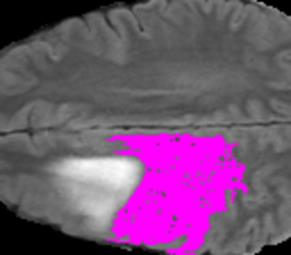

Weakly Supervised Semantic Segmentation (WSSS) relying only on image-level supervision is a promising approach to deal with the need for Segmentation networks, especially for generating a large number of pixel-wise masks in a given dataset. However, most state-of-the-art image-level WSSS techniques lack an understanding of the geometric features embedded in the images since the network cannot derive any object boundary information from just image-level labels. We define a boundary here as the line separating an object and its background, or two different objects. To address this drawback, we are proposing our novel ReFit framework, which deploys state-of-the-art class activation maps combined with various post-processing techniques in order to achieve fine-grained higher-accuracy segmentation masks. To achieve this, we investigate a state-of-the-art unsupervised segmentation network that can be used to construct a boundary map, which enables ReFit to predict object locations with sharper boundaries. By applying our method to WSSS predictions, we achieved up to 10% improvement over the current state-of-the-art WSSS methods for medical imaging. The framework is open-source, to ensure that our results are reproducible, and accessible online at https://github.com/bharathprabakaran/ReFit.